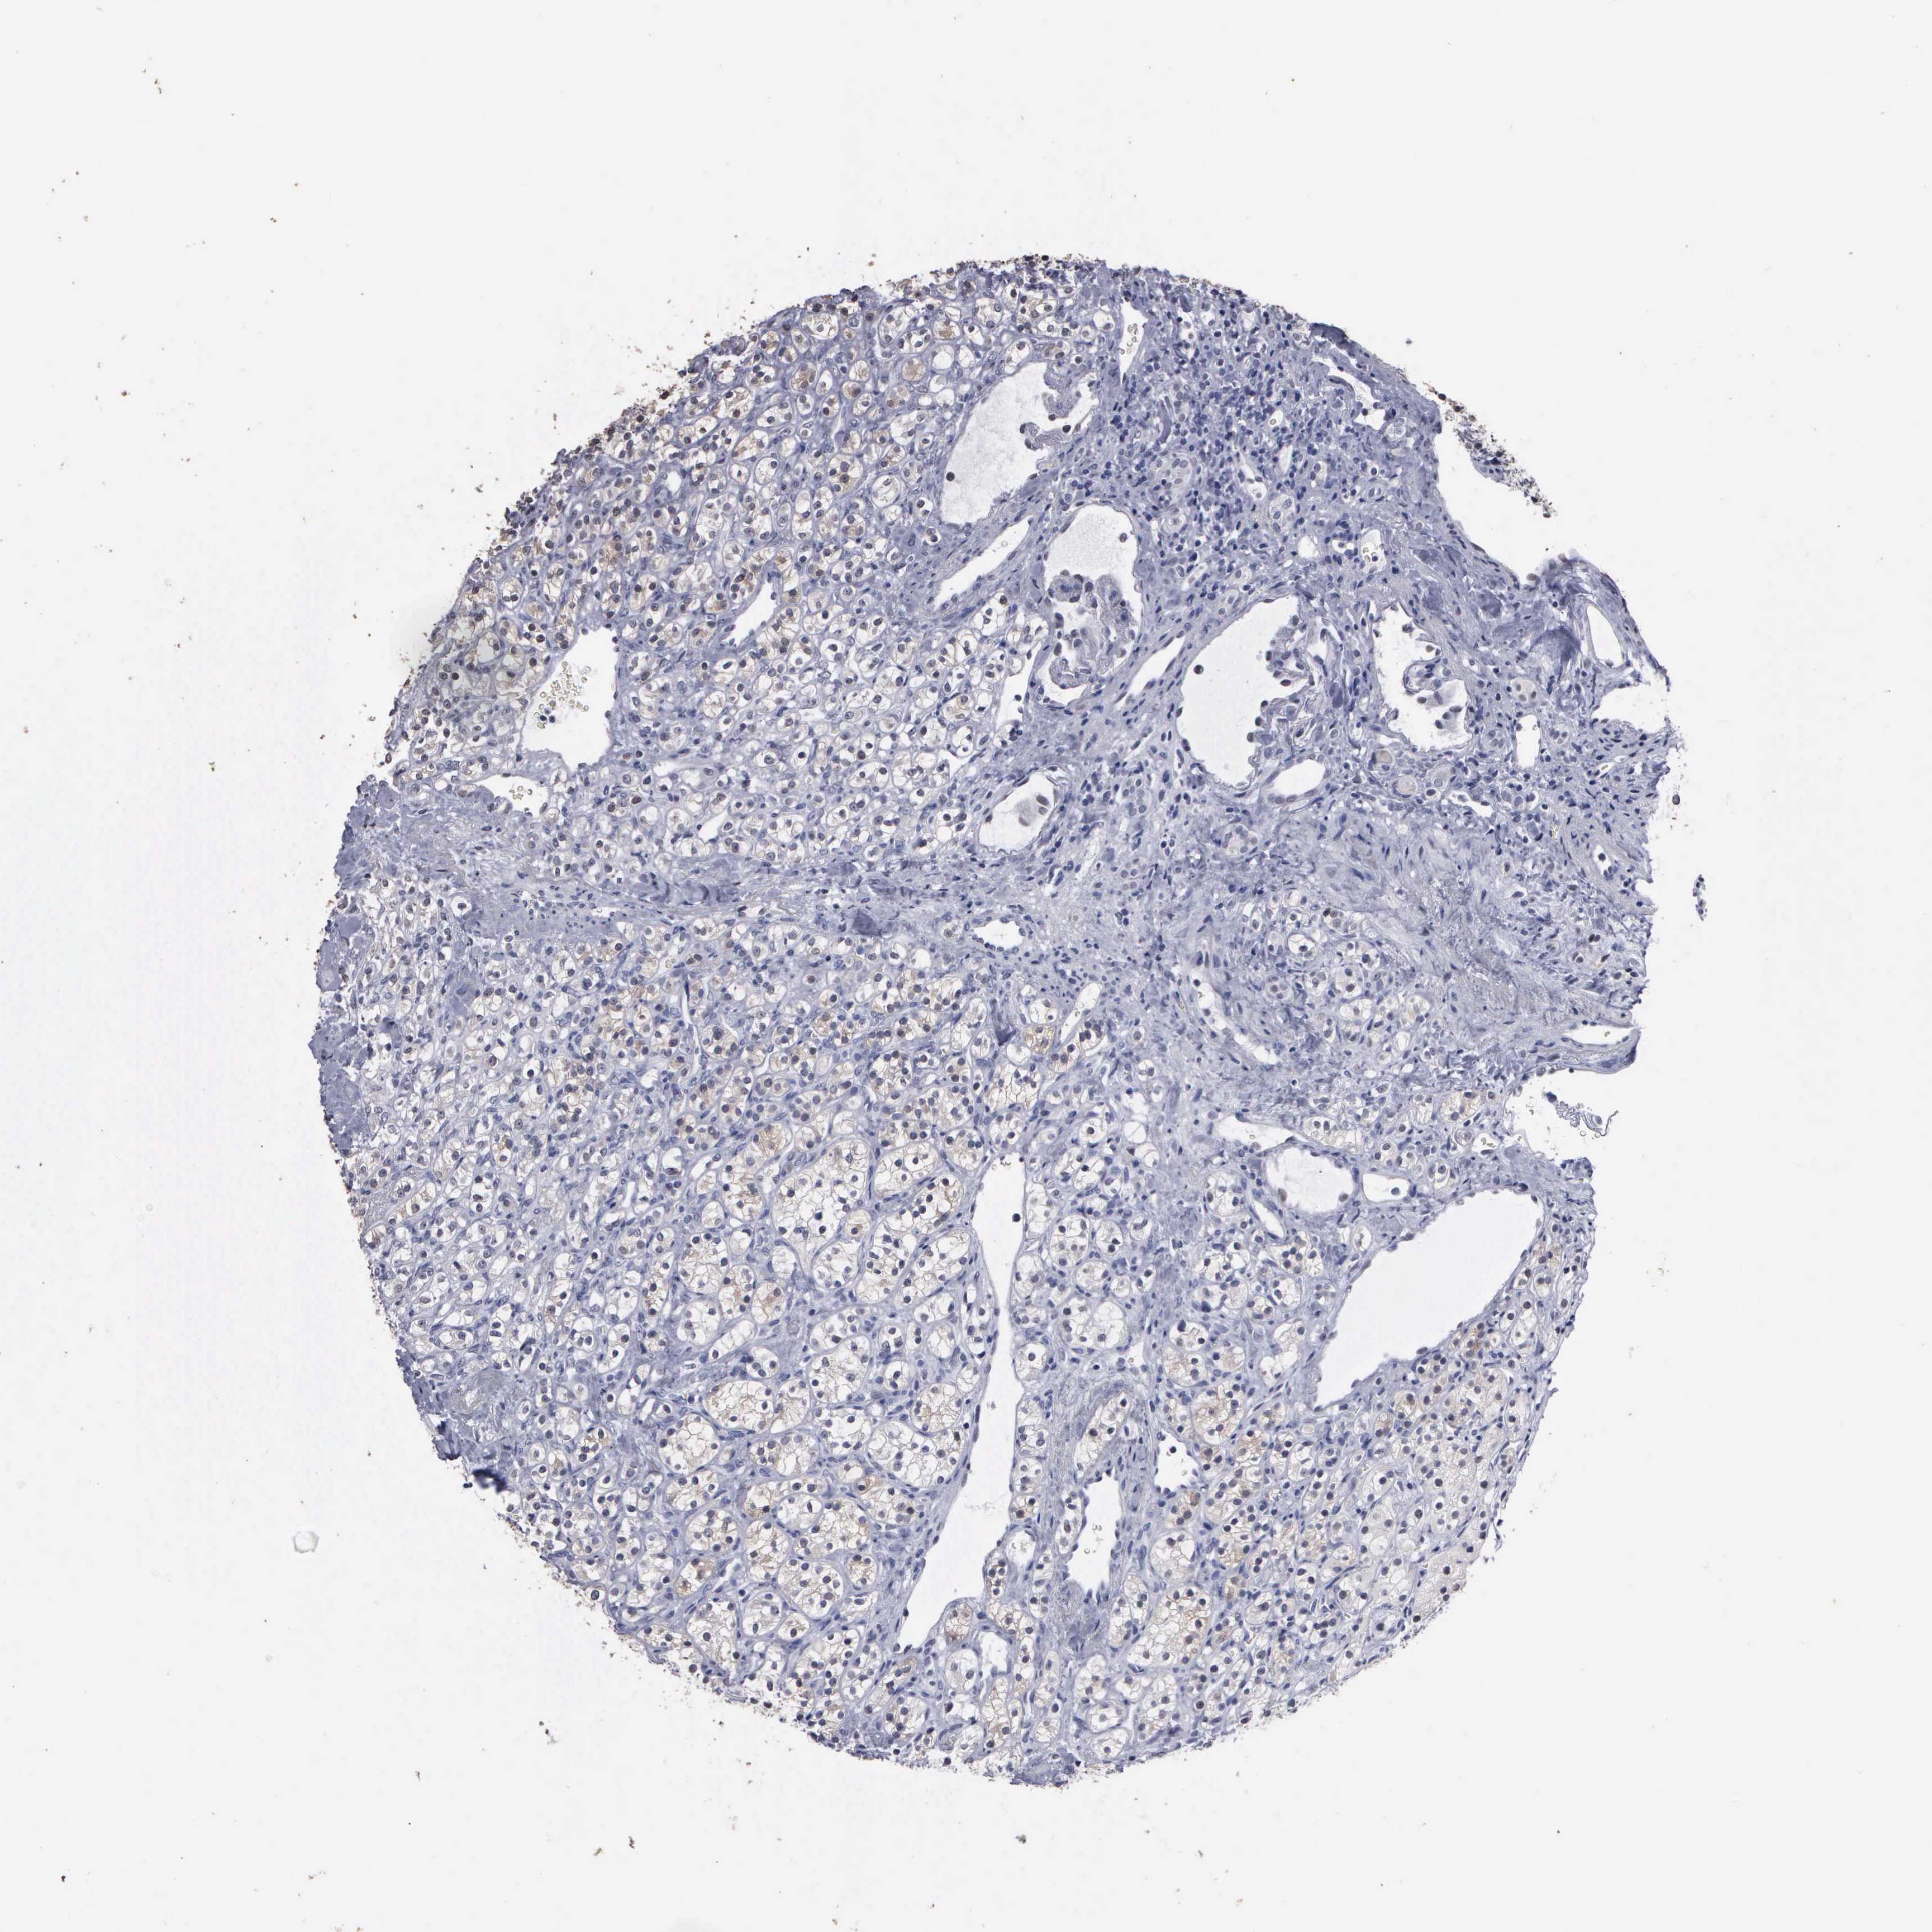

CANCER RENAL CANCER Show tissue menu

KICH TCGA KIRC TCGA KIRC VALIDATION KIRP TCGA PROTEIN RCC CPTAC PROTEIN EXPRESSION